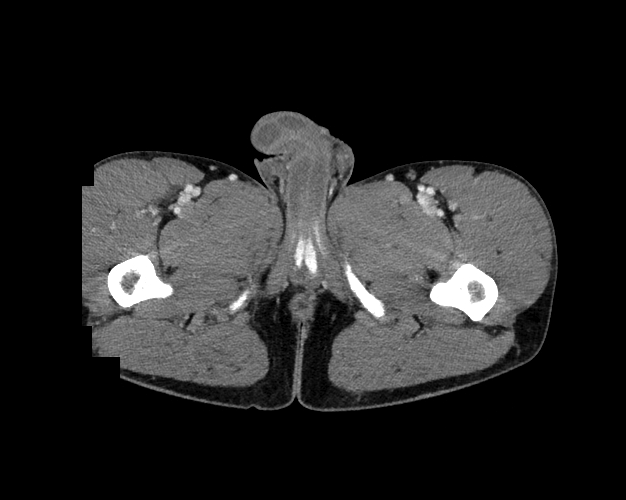

Body

Covers abdominal CT anatomy.